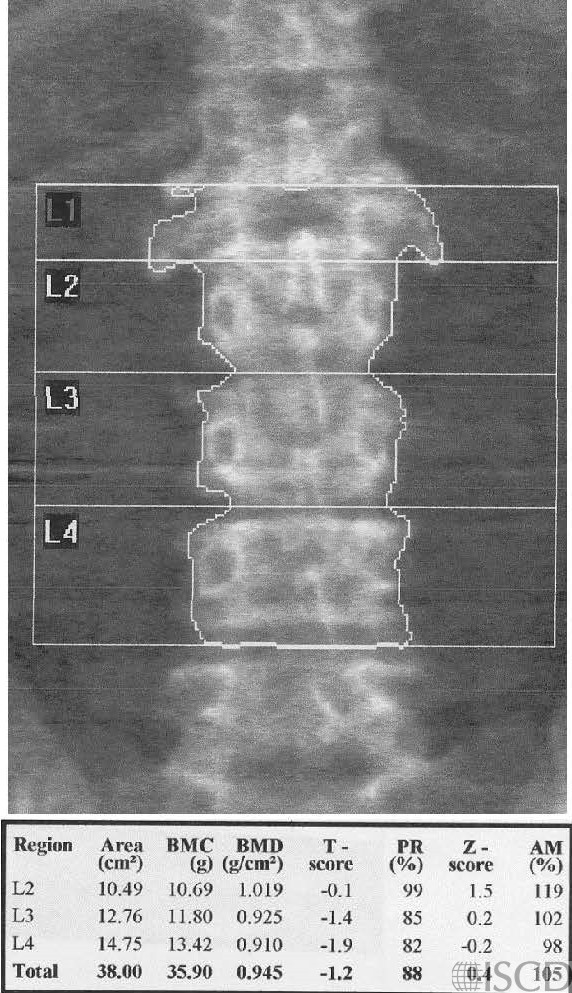

There is a black hole artifact over L4, therefore it was omitted from analysis. There are black hole-type artifacts over L4 and in the soft tissue.

This Hologic lumbar spine DXA scan shows a black hole-type artifact over L4. Items like lead bullets and tantalum clips show up as “black”on Hologic scans. The accompanying radiograph shows the clips over L4. L4 is omitted because of overlying artifacts.

Black hole artifacts occur with dense metals such as lead and tantalum on a Hologic scan. Other metals, like stainless steel, don’t produce black hole artifacts. Presumably there is complete attenuation of both Kev peaks so the difference is zero, making the image appear black. Lead bullets are measured as having high bone mineral content (BMC) and appear black in the dual-energy mode on the Hologic scanner and blue as artifact on GE Healthcare scanners. Black hole artifacts over bone are handled differently between Hologic and General Electric. With the Hologic scanner, when a dense artifact overlies bone, the BMC associated with that artifact is excluded, but the bone area is not altered. Consequently, the bone mineral density (BMD) of the affected vertebra, and of L1-4 is decreased. The GE scanners exclude both the associated BMC and area covered by the artifact, thereby minimizing the impact on BMD. Dense artifacts in the soft tissue do not significantly affect BMD on either manufacturer’s densitometer on phantom experiments., however, further experiments need to be done to verify this finding.